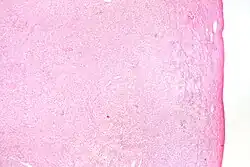

| High magnification micrograph of a thecoma. H&E stain. | |

Pathologic features

Grossly, the tumour is solid and yellow.

Grossly and microscopically, it consists of the ovarian cortex.

Microscopically, the tumour cells have abundant lipid-filled cytoplasm.